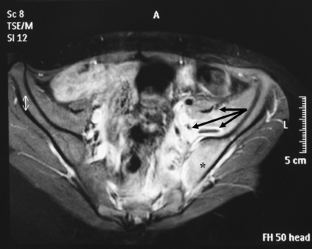

Fig. 1

Fig. 2